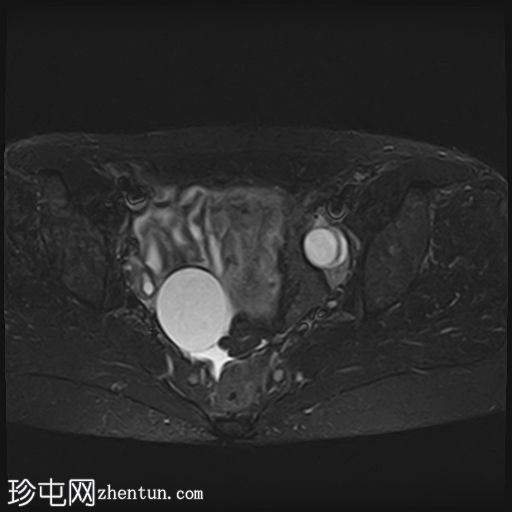

轴向

STIR

卵巢相关囊性病变边界相对清晰。信号特征可能因出血时间而异。

T2 加权成像通常显示高信号。 T2 阴影征提示存在慢性血液产物,更像子宫内膜异位症。

本例卵巢囊肿呈中等 T1 信号,类似于肌肉信号,T2 信号高,伴有薄内隔和外周壁强化。但无内部强化或弥散受限。STIR 序列显示与 T2 一致的信号,无任何脂肪成分。该表现提示卵巢出血性囊肿处于早期或消退期。